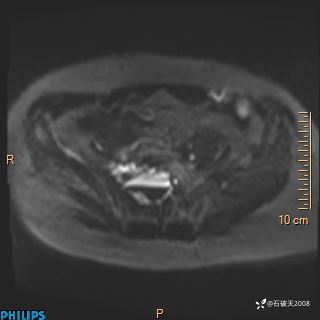

2023年3月份MRI影像

增强轴位